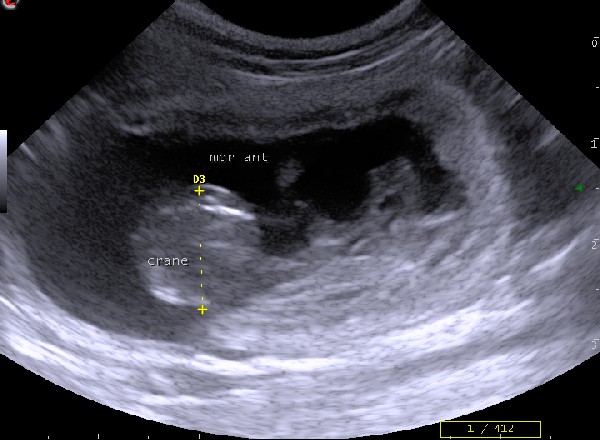

Comme en médecine humaine, vos compagnons peuvent bénéficier de cette technique d'imagerie totalement indolore permettant la visualisation des organes internes :

• échographie de l'appareil génital (dont la prostate)

• échographie de l'appareil urinaire (reins, vessie)

• échographie de la rate

• échographie de l'appareil digestif                            (estomac, intestin, foie, pancréas)